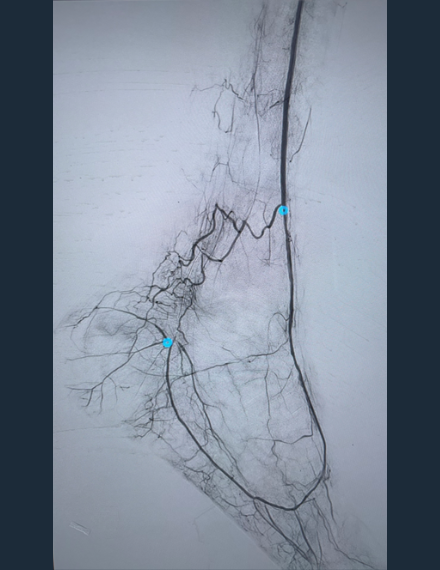

Post-Shockwave Javelin Angio

Restored patency to distal AT, DP and pedal-plantar loop -

Final Angio

Brisk flow restored throughout treated vasculature

Pre-procedural vascular testing showed absent great-toe pressure, occlusion of the distal anterior tibial and dorsal pedal arteries, and a patent but low-velocity bypass graft with poor distal outflow consistent with chronic limb-threatening ischemia. The distal AT and DP lesions were traversed intraluminal and Shockwave Javelin was used to modify the heavily calcified plaque followed by a percutaneous transluminal angioplasty (PTA) balloon.